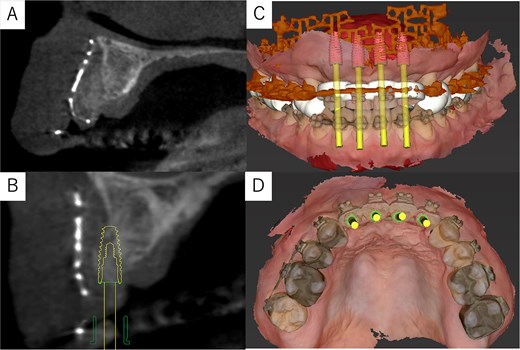

Post-surgery cone-beam computed tomography and implant simulation. (A) Cone-beam computed tomography at 2 months postoperatively confirmed grafted bone stability. (B) Simulation of dental implant placement with a sagittal cross-sectional cone-beam computed tomography image. (C) Frontal view of implant placement. (D) Occlusal view of implant placement.

The postoperative panoramic radiograph showed no abnormalities (Fig. 4C). Cone-beam computed tomography images taken 2 months after surgery confirmed the stability of the grafted bone (Fig. 5A). A new simulation for dental implant placement was performed (Fig. 5B–D). At 4 months postoperatively, the titanium mesh was removed, and dental implants were placed. Bone tissue in the defect was confirmed. Implants with a diameter of 4.1 mm and a length of 10 mm (Straumann BLT/RC; Straumann, Basel, Switzerland) were successfully inserted (Fig. 6A–C). Postoperative photographs (Fig. 7) showed improvement in the skeletal mandibular protrusion and a favorable intermaxillary relationship between the upper and lower jaws.